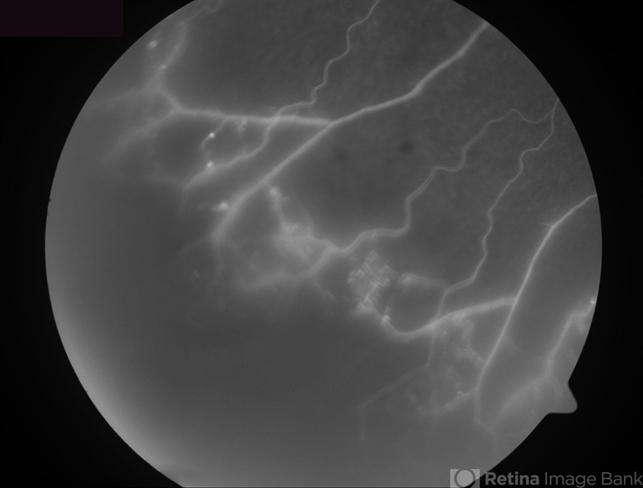

- Ischemic Branch Retinal Vein Occlusion

- branch retinal vein occlusion (BRVO), capillary nonperfusion

- Fluorescein angiogram of the inferotemporal periphery showing wide areas of capillary nonperfusion.